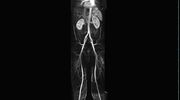

MR-Angiografie (MRA)

• MR-Angiografie ohne Kontrastmittel

• Time of Flight (TOF)-Angiographie

Je nach Fragestellung und Körperregion Gefäßdarstellung ohne Kontrastmittel bei Kontrastmittelunverträglichkeit oder terminaler Niereninsuffizienz möglich.

• MR-Angiographie mit Kontrastmittel

• Erfassung arterieller und venöser Gefäße/Bypässe aller Körperregionen mit 3D-Rekonstruktion